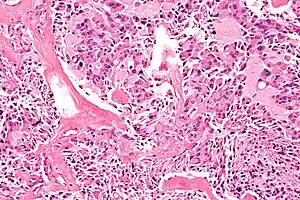

Multiple Endocrine Neoplasia type 1 (MEN1) is a rare hereditary endocrine cancer syndrome characterized primarily by tumors of the parathyroid glands (95% of cases), endocrine gastroenteropancreatic (GEP) tract (30–80% of cases), and anterior pituitary (15–90% of cases).[19] Other endocrine and non-endocrine neoplasms including adrenocortical and thyroid tumors, visceral and cutaneous lipomas, meningiomas, facial angiofibromas and collagenomas, and thymic, gastric, and bronchial carcinoids also occur. The phenotype of MEN1 is broad, and over 20 different combinations of endocrine and non-endocrine manifestations have been described. MEN1 should be suspected in patients with an endocrinopathy of two of the three characteristic affected organs, or with an endocrinopathy of one of these organs plus a first-degree relative affected by MEN1 syndrome.

Many endocrine tumors in MEN1 are benign and cause symptoms by overproduction of hormones or local mass effects, while other MEN1 tumors are associated with an elevated risk for malignancy. About one-third of patients affected with MEN1 will die early from MEN1-related cancer or associated malignancy. Entero-pancreatic gastrinomas and thymic and bronchial carcinoids are the leading cause of morbidity and mortality. Consequently, the average age of death in untreated individuals with MEN1 is significantly lower (55.4 years for men and 46.8 years for women) than that of the general population.